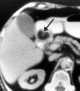

Gastric ulceration

May Be Caused by